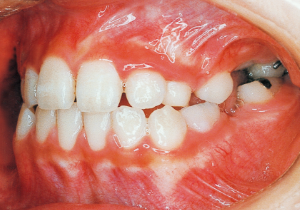

Age at Initial Visit: 8 years 1 month, Female / Protruding lower bite. Protruding lower jaw

1 Initial Visit 8-29-’79

Although there were many missing deciduous teeth, the number of permanent teeth was not problematic (4). The amount of negative overjet was significant (1). On cephalometric radiographs, the mandibular ramus was not relatively long, but the large gonial angle and the long mandibular body were noticeable, indicating an overall tendency of the mandible to project inferiorly and anteriorly. High lower facial height was also characteristic.

A potential predisposition to mandibular protrusion was clearly evident.